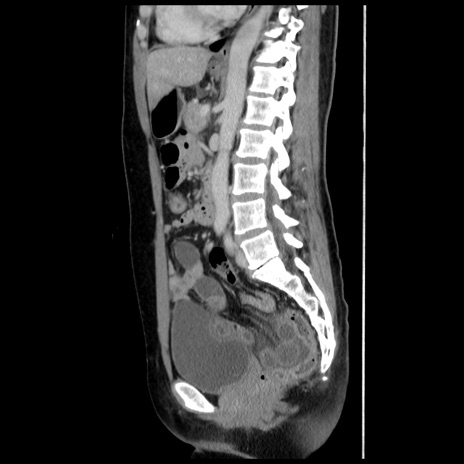

症例10(矢状断像)

【症例】 50歳代女性

【主訴】 腹痛

【現病歴】前日生レバーを食べた。今朝に排便あり。 昼前に突然発症の腹痛を生じ、当院救急外来を受診した。

【既往歴】 子宮筋腫にてで子宮全摘後

【身体所見】 意識清明、腹部:平坦、軟、下腹部やや左を中心に圧痛・反跳痛あり、筋性防御あり

【データ】WBC 7800、CRP 0.07